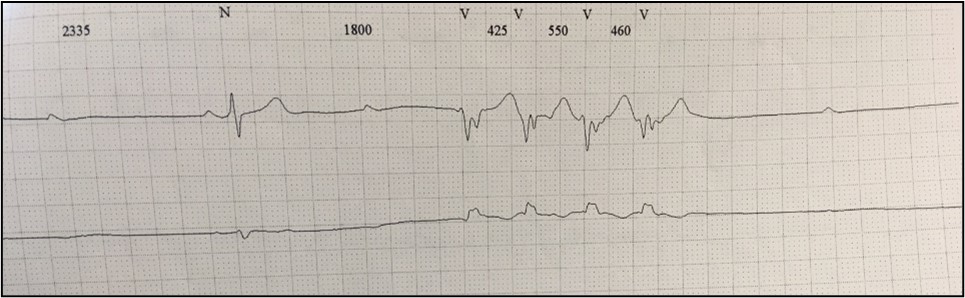

The transthoracic echocardiography showed a slightly dilated (115/70 mL) left ventricle (LV), with normal wall thickness, global hypokinesia and mildly reduced LVEF (45%). The left atrium was dilated (45 mm). Also, the right ventricle was dilated (45 mm) with preserved systolic function (Figure 3).

Clinical case_ Fig 3 - The importance of early etiologic diagnosis of dilated cardiomyopathy.png